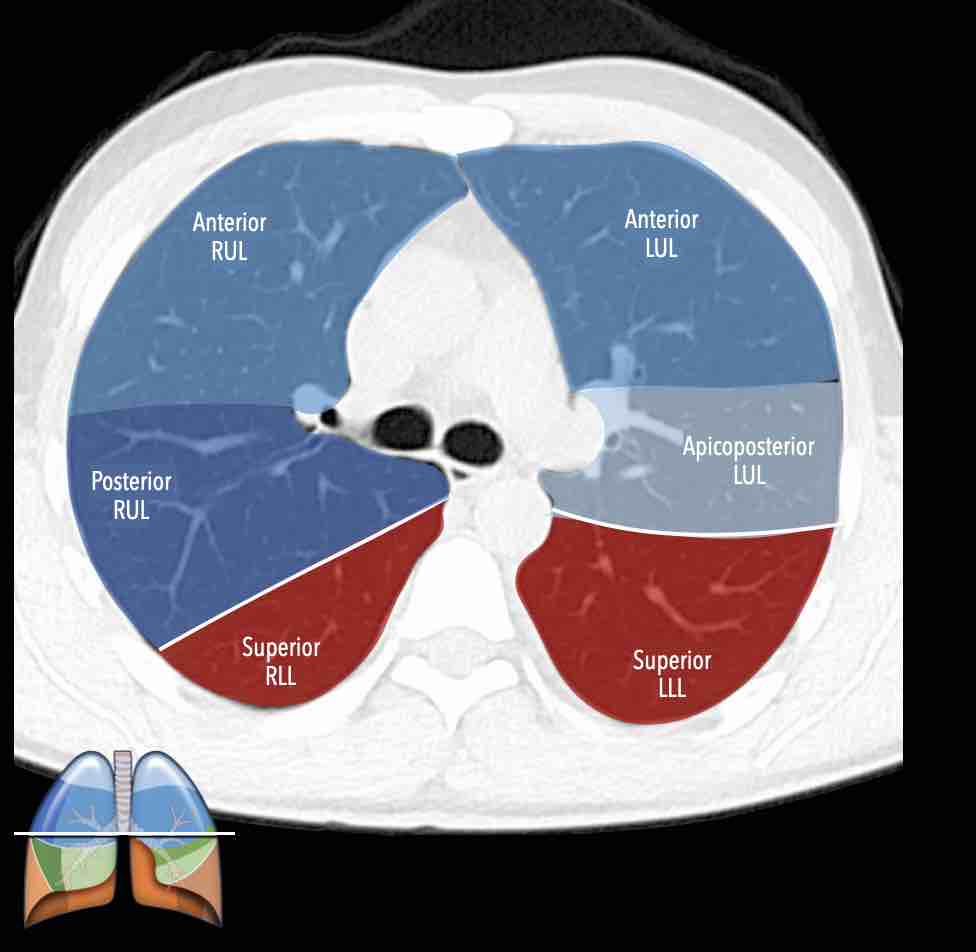

Các phân thùy phổi trên CT

Cuộn qua các hình ảnh để quan sát cách phổi được phân chia thành các phân thùy.